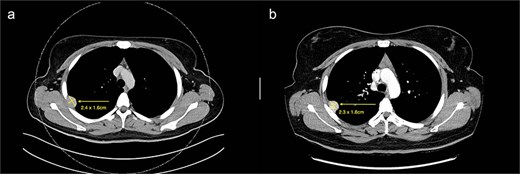

(a) Axial cut of CT thorax taken in April 2024, depicting a right sided hyperdense peripheral pleural lesion measuring 2.4 × 1.6 cm. (b) Axial cut of a repeat CT thorax taken in February 2025, showing the same hyperdense pleural lesion relatively stable in size, now measuring 2.3 × 1.8 cm.

From a clinical perspective, given the uncertain malignant potential of GLI1 fusion-associated tumours, and in the context of her ongoing adjuvant chemotherapy (8 cycles of XELOX for 6 months) for colorectal adenocarcinoma, surgical management of the pleural lesion was deferred. Serial imaging over 10 months demonstrated tumour stability in size (2.3 × 1.8 cm), suggesting indolent behaviour (Fig. 1b). However, in view of the histological ambiguity and lack of established prognostic markers, despite the seemingly benign behaviour, a shared decision was made to proceed with surgical excision.